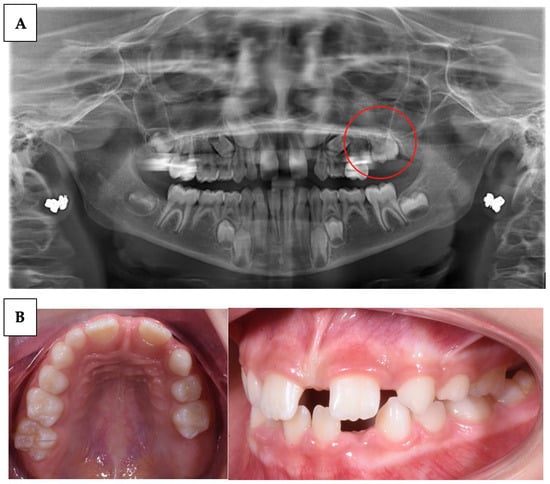

| Wagner et al. (2023) [59] | Case series | 3 | Describe the variability of clinical presentations of PFE associated with pathogenic variants of PTHR1 | Clinical examination, radiological examination, and molecular DNA testing | Multidisciplinary complex treatment, from child to adulthood. |